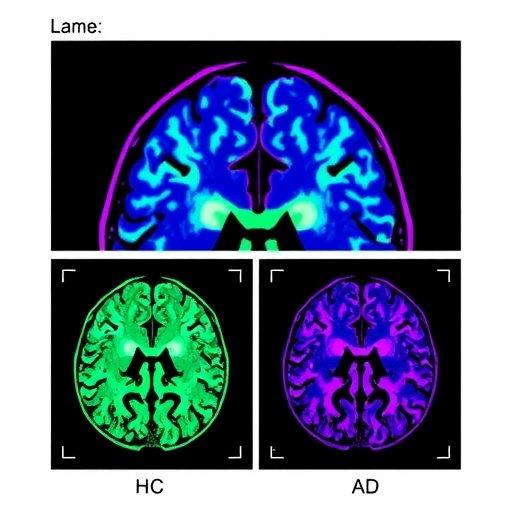

An impressive aspect of the study is its emphasis on the explainability of the AI model. The researchers prioritized not only accuracy but also the interpretability of the findings. Understanding the reasons behind a model’s predictions can significantly aid clinicians in making more informed decisions regarding patient care. By employing techniques such as heatmaps, the researchers could visually represent the specific areas of the brain that contributed most significantly to the classification, thus providing essential insights for clinical practitioners.